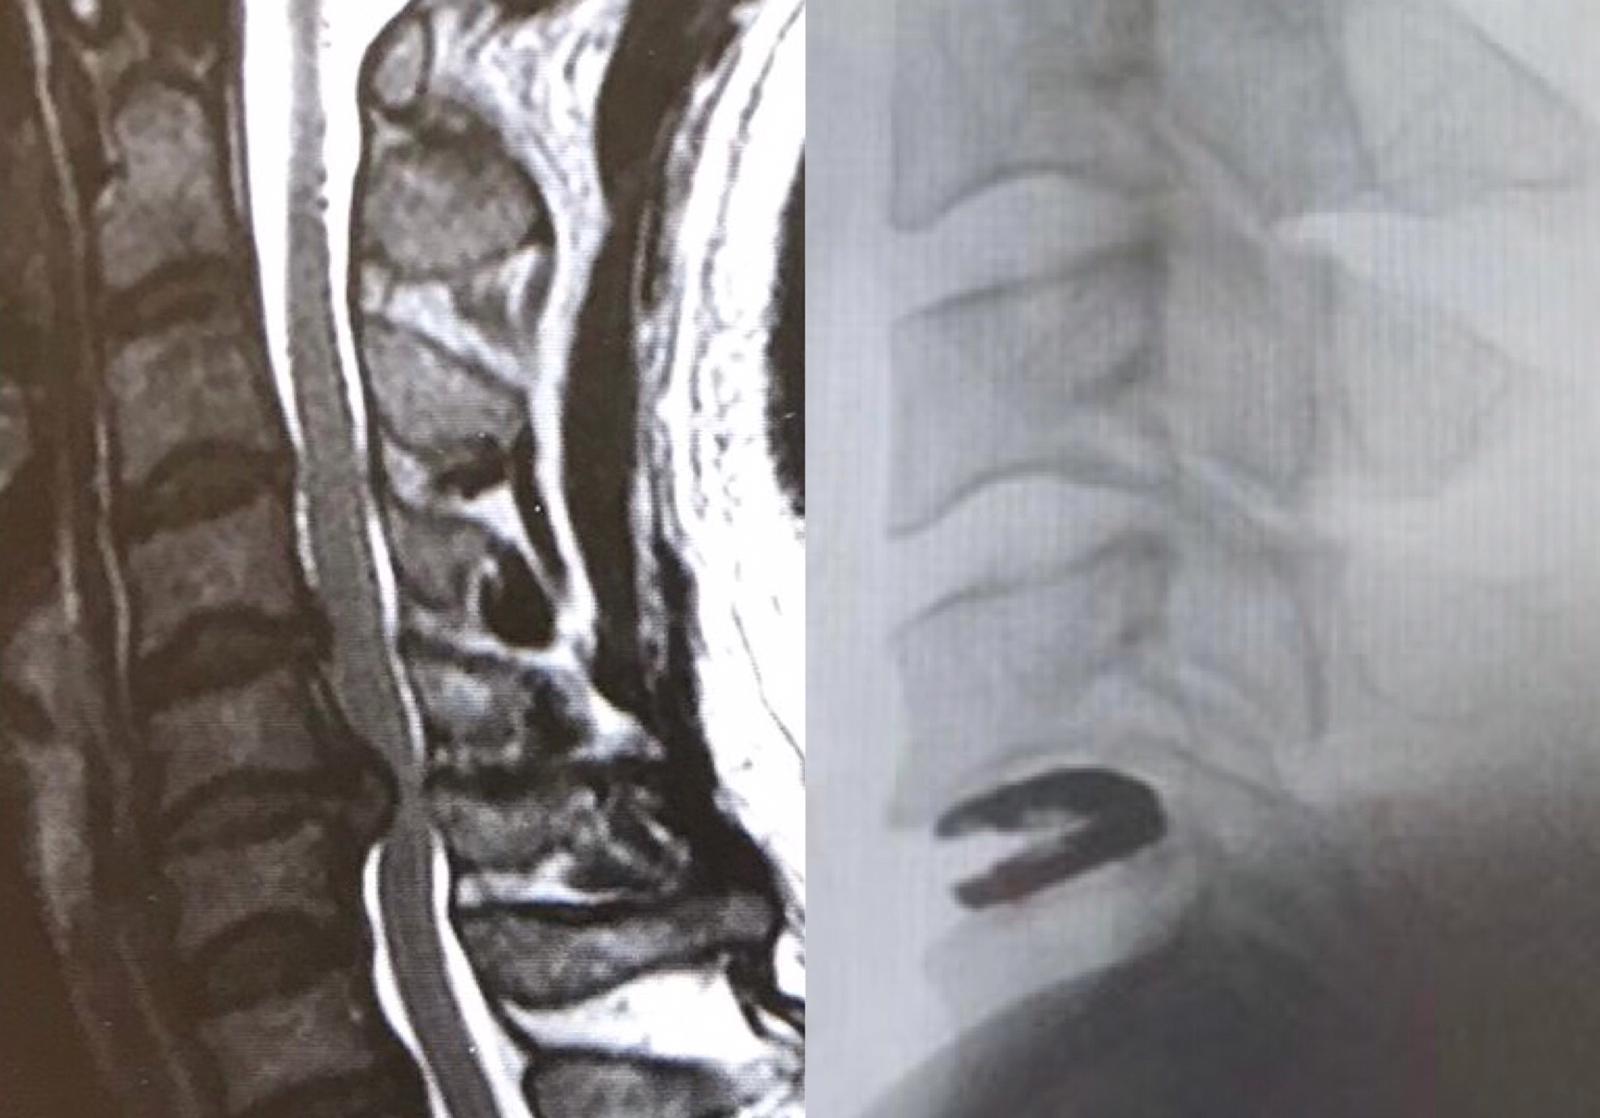

故此,筆者時常提醒讀者避免成為低頭族,以防頸椎提早退化,也建議手腳麻痺無力的人士盡早求診。若懷疑患上脊髓型頸椎病,更需照磁力共振來評估嚴重程度。萬一脊髓受壓過久,完全復元的機率便大大降低。及早做手術為脊髓減壓,能避免日後惡化至須靠輪椅代步。手術大致可分為「前路」減壓及融合術,並「後路」減壓及椎板成形或切除術,視乎多少節脊髓受壓,並頸椎有否出現後凸畸形而決定開刀路徑。